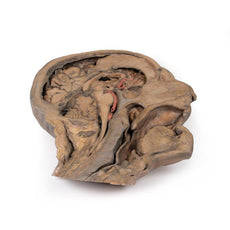

3D Printed Brain Hemisection

This 3D model is a midsagittal hemisection through a whole brain, preserving the right side anatomy and deep brain

structures and spaces visible in the midline. In lateral view, the right cerebral and cerebellar hemispheres are

covered in the arachnoid mater. In the midline view, the brain regions from the cerebrum to the medulla oblongata

are preserved. Centrally, the third ventricle is opened, with an intact septum pellucidum superiorly positioned and

obscuring the lateral ventricles within the cerebral hemisphere. On the inferior margin of the third ventricle both

the right mamillary body and right optic tract can be observed, whereas posteriorly the cerebral aqueduct can be

observed extending across the midbrain between the tectum and tegmentum towards the fourth ventricle (between the

cerebellum and pons). The cerebellum is separated from the occipital lobe by a preserved portion of the tentorium

cerebelli, and in cross-section the cerebellar cortex helps form the prominent arbor vitae.

A series of arterial

branches have been false coloured to contrast their course across the preserved brain structures. In the midsagittal

view the anterior cerebral artery courses from around the corpus callosum to supply the cingulate gyrus and other

midline cortical regions. The base of the middle cerebral artery can be seen passing deep between the temporal and

frontal lobes, with the posterior communicating artery connecting it to a small remnant of the posterior cerebral

artery. Adjacent to the posterior cerebral is the superior cerebellar artery, extending laterally to pass between

the temporal lobe and the cerebellum before passing deep into the transverse fissure.